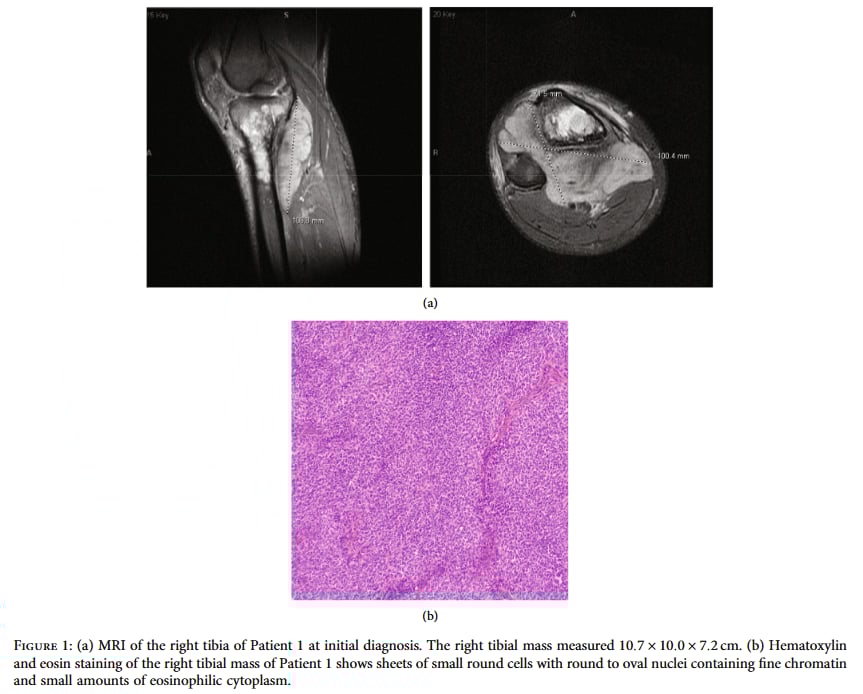

患者情况:一名16岁的男孩,因右小腿持续疼痛和肿胀6个月而就医。影像学检查(X光和MRI)显示,他的右侧胫骨上段有一个巨大的肿瘤,尺寸约为10.7×10.0×7.2厘米,并且已经侵犯到周围的肌肉组织,甚至转移到了盆腔的淋巴结。

▲图1 初诊时的MRI和HE染色结果

诊断难题:医生对肿瘤进行了活检。病理结果显示这是一种“低分化小圆细胞肉瘤”。进一步的免疫组化检测发现,肿瘤细胞的CD99、BCOR、FLI1等多个指标呈阳性,但一个对尤因肉瘤非常关键的指标NKX2.2却是阴性。基于这些“矛盾”的信号,初步诊断倾向于一种罕见的“尤因样肉瘤”(Ewing-like sarcoma, ELS),特别是BCOR::CCNB3融合亚型。

NGS的决定性作用:尽管尤因样肉瘤和尤因肉瘤(Ewing Sarcoma, ES)的治疗方案目前相似,但它们的生物学行为和长期预后存在差异。为了得到最准确的诊断,医生团队决定采用基于RNA的NGS检测。结果令人振奋:NGS检测清晰地识别出了尤因肉瘤的标志性基因融合——EWSR1基因与FLI1基因的融合。这个发现如同一把钥匙,打开了诊断的僵局,最终将诊断修正为经典的“尤因肉瘤”。